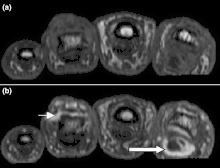

Magnetic resonance images of the fingers in psoriatic arthritis. Shown are T1 weighted axial (a) pre-contrast and (b) post-contrast images exhibiting dactylitis due to flexor tenosynovitis at the second finger with enhancement and thickening of the tendon sheath (large arrow). Synovitis is seen in the fourth proximal interphalangeal joint (small arrow). -